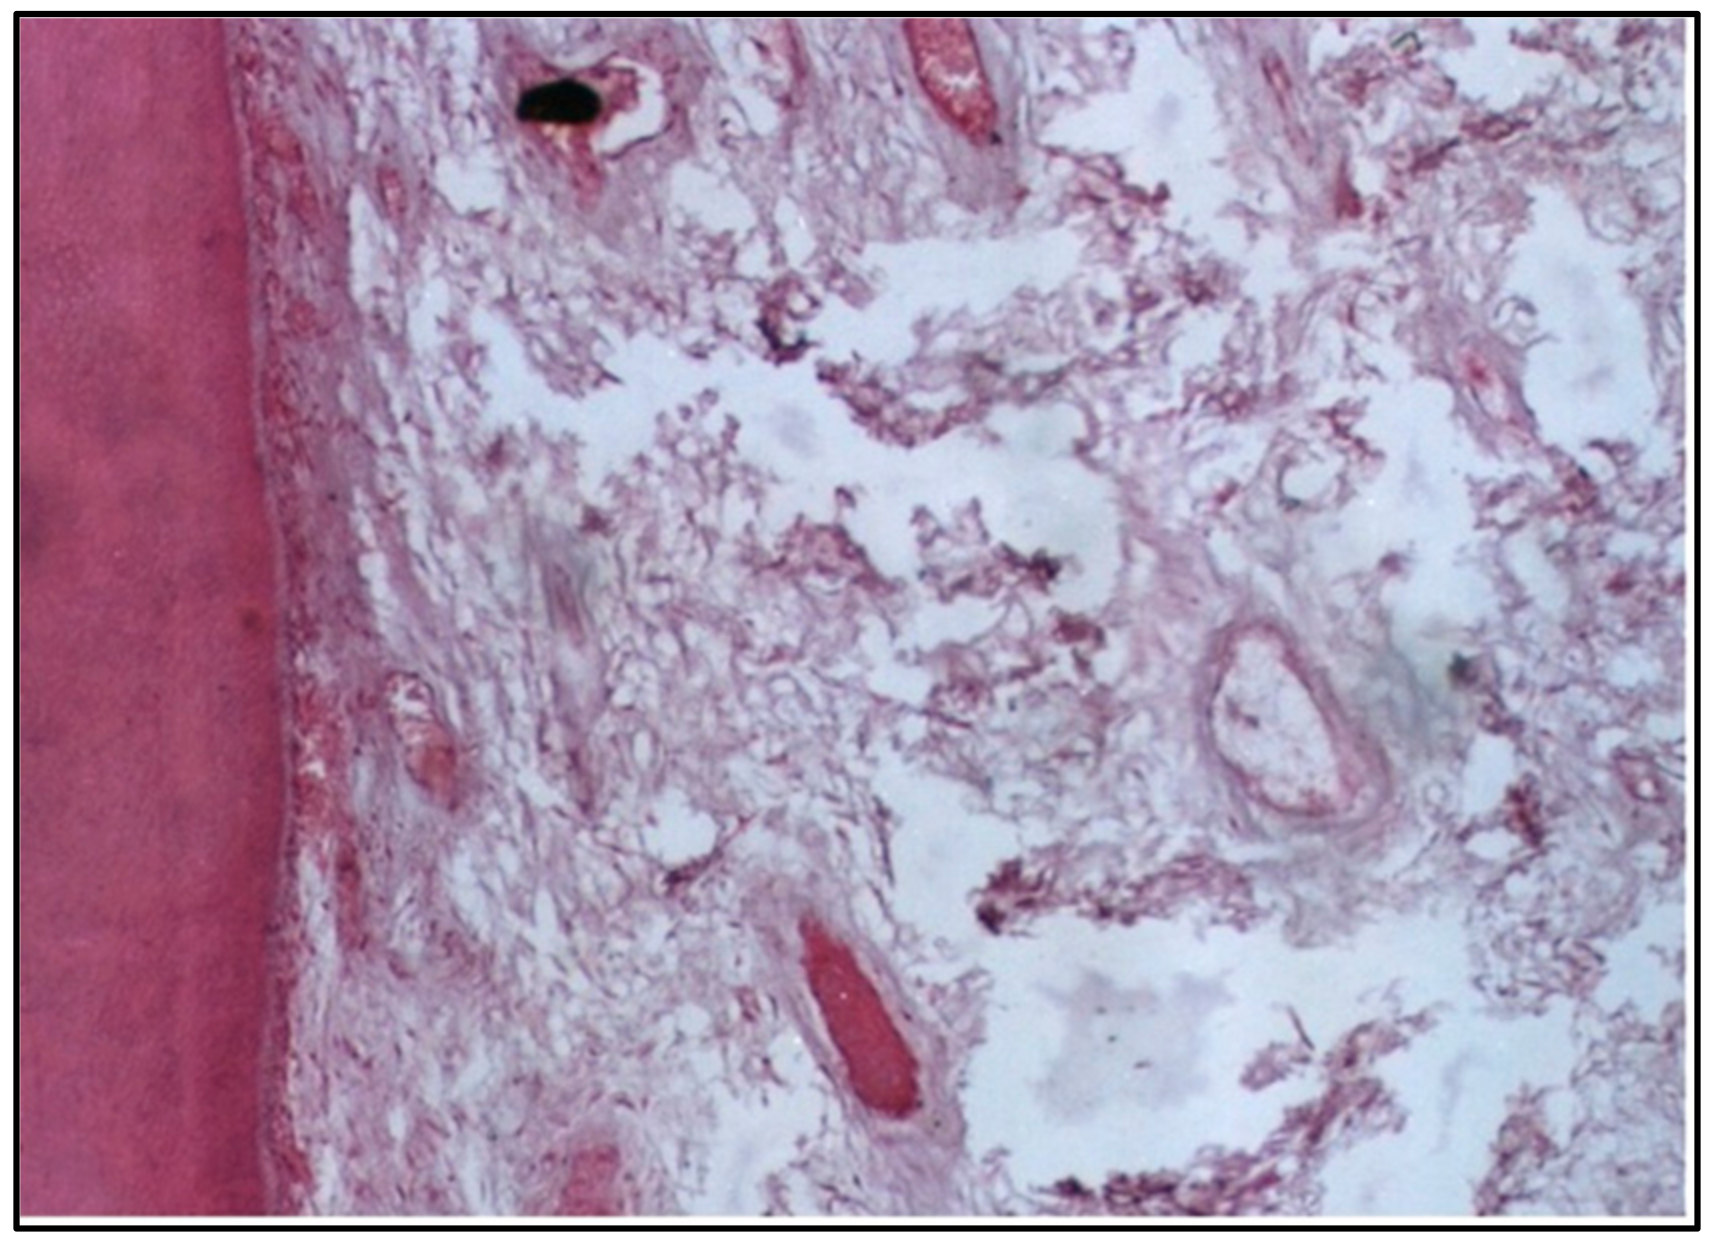

At 2 weeks, the pulp tissue displayed moderate disorganization, but the pattern of damage was more localized compared with Group I. The cells and fibers at one side of the tissue were condensed, which could indicate fibrosis, a common reaction to injury. Meanwhile, the central area was more loosely arranged, reflecting ongoing inflammation (Figure 3). Notably, one of the specimens had a microabscess formation, signifying localized pus accumulation due to infection or significant inflammation, which was more severe than the vascular changes observed in Group I (Figure 4).

At 6 weeks, the damage was even more severe, with massive destruction of the pulp tissue, including the formation of a large abscess. This level of destruction indicates that the pulp could not withstand the long-term effects of the conventional composite resin, leading to extensive tissue necrosis and infection (Figure 5).

At 6 weeks, the situation had worsened, with massive pulp tissue destruction and abscess formation observed. This suggests an inability of the pulp tissue to recover from the initial insult, leading to progressive necrosis and infection. The persistence of such reactions over time might be related to factors such as incomplete polymerization and the leaching of unreacted monomers [19].

The severe pulp response observed in one specimen with conventional composite resin was manifested by the presence of dense inflammatory cell accumulation and localized abscess formation beneath the cavity. This observation could be due to the presence of bacterial contamination during the filling procedure and/or microleakage and the long–standing bacteria and their endotoxins at the restoration/tooth interface. This finding has also been observed by Riberio et al. [20]. In contrast, the control group exhibited normal cellularity, vascularity, and odontoblast alignment at both 2 and 6 weeks. This highlights the natural regenerative capacity of the pulp tissue in the absence of irritants, reaffirming the importance of selecting biocompatible materials for restorative procedures [21].

Figure 5. LS of the pulp (Group II, 6 weeks) showing massive destruction of the pulp tissue with an abscess formation (H & E Stain, ×100).